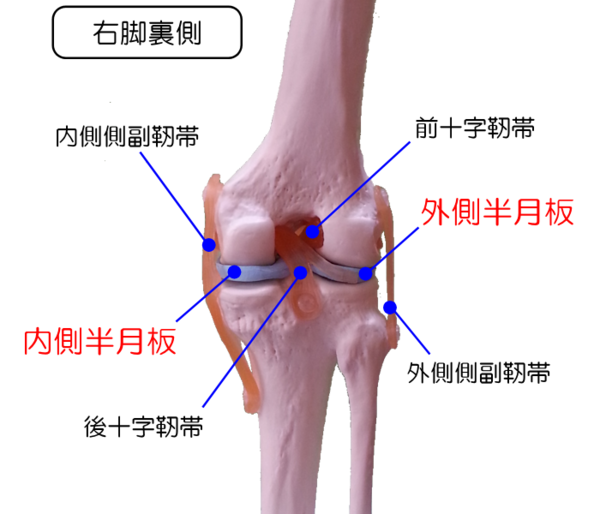

怪我といえば、去年の9月に半月板のひび割れで、医者に手術しないと治らないといわれましたが、

その後3ヶ月間は安静と自前のレーザーで様子を見てました。

痛みが全然消えなければ、手術の予定でしたが、1年後の今では普通にテニスもゴルフも出来るし、念願の70台も出ました。

半月板損傷

9月は連休も重なり二週続けて久々にテニス大会に参加しました。

結果は準優勝と優勝となり大満足でしたが、

当日、数年前から違和感があった膝に激痛がおこりました。

数日過ぎても、痛みは引かず、膝専門の整形外科に診てもらうと、

右ひざ半月板の損傷ということで、手術しないと治りませんといわれ大ショック!

どうしようか検討中です。

歩行中も痛みがあるので、テニス、ゴルフはしばらくお預けです(泣)。

どちらが原因?

半月板を損傷して一ヶ月以上経ちますが、まだ痛みが引くどころか、

愛犬(ラッキー)との散歩も行けず、寝ている時に痛みで目が覚めたりしています。

この前、NHKで膝専門のスーパードクターが人工関節のオペで歩けるようにしていました。

私が受診した整形外科の医師からも手術を勧められましたが、ここで気になったのが、